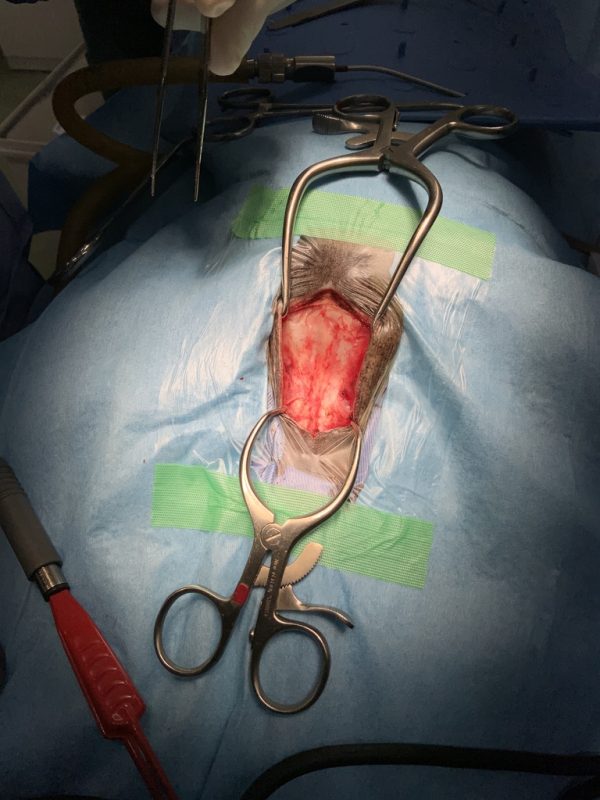

再手術

2025年12月14日(日)

CT検査の結果がいつもお世話になっている病院へ届いて、院長先生から明日か明後日でも手術できると連絡があった。急だが年末もあるので、今日病院に連れて行って明日土曜日に手術してもらうことにした。

2025年12月15日(土)

手術は15時すぎから1時間半ほどでおわったようです。